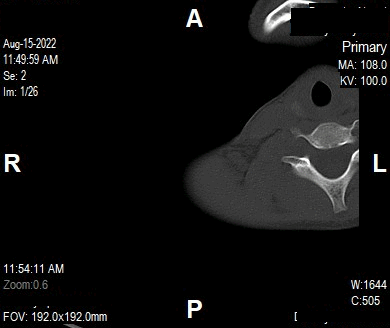

Appearance of Shoulder in Axial CT Image

CT Elbow (Axial Images)